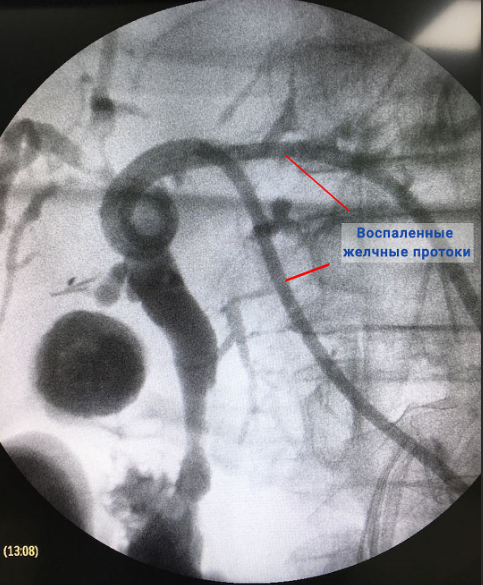

В рамках диагностики холангита также могут проводиться инструментальные исследования, такие как УЗИ органов брюшной полости, магнитно-резонансная холангиопанкреатография (визуализация желчного пузыря, желчных протоков, печени, поджелудочной железы), эндоскопическая ретроградная холангиопанкреатография, эзофагогастродуоденоскопия (осмотр органов пищеварительной системы при помощи зонда гастроскопа) и др. Методы визуализации позволяют выявить расширения и сужения желчных протоков, установить размеры органов гепатобилиарной системы и получить другие важные диагностические данные. При подозрении на холангит может быть назначена биопсия печени.